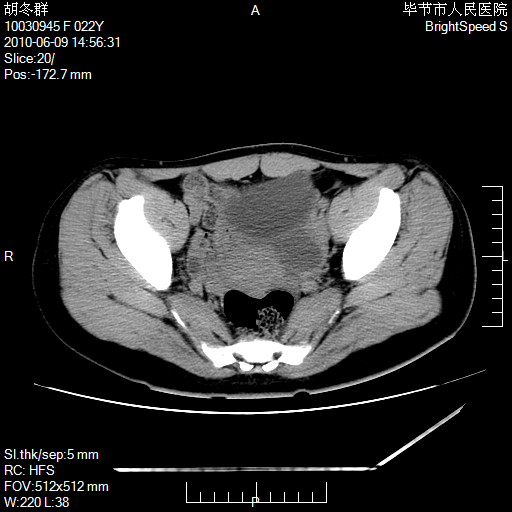

患者23岁,发现腹部包块3月。

盆腔内囊性占位;穿刺或者直接手术拿掉即可,不必紧张。

左侧卵巢囊腺瘤或囊腺癌

盆腔内囊性占位性病变;考虑左侧卵巢囊腺瘤。

有分隔、壁薄,支持考虑左侧卵巢囊腺瘤。

左侧卵巢浆液性囊腺瘤。

支持考虑左侧卵巢囊腺瘤;宫腔积液。